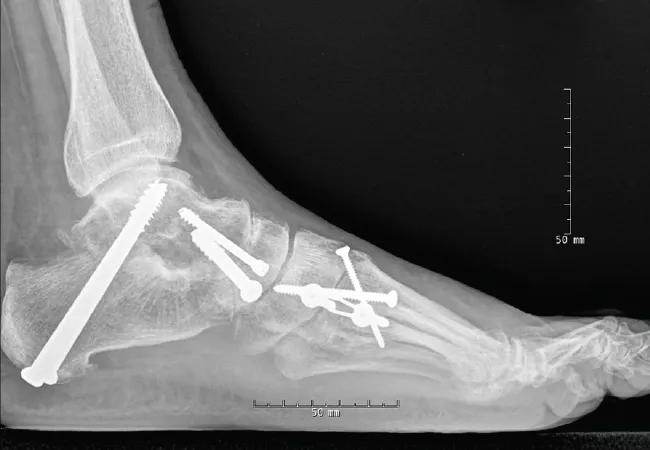

Over the past five years, 34 patients have undergone this modified triple surgery for the correction of a severe flatfoot. This cohort is being formally evaluated for patient satisfaction and functional outcome, and we hope to publish results of this study in the near future. To date, no patient has developed a nonunion and both radiographic and clinical correction has been significant (Figures 2A, 2B).

16-ORT-630-Berkowitz-Inset-Part-B

Figures 2. Postoperative AP and lateral radiographs demonstrate correction of all components of flatfoot deformity with modified triple arthrodesis.